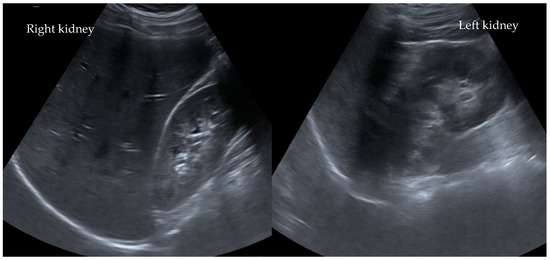

In addition, both potassium and C-reactive protein (CRP) levels were highly elevated at 6.3 mmol/L and 4.0 mg/dL, respectively. All other laboratory tests were within the normal range. Interestingly, an abdominal ultrasound revealed no abnormalities (Figure 1). Due to the suspicion of an acute abdomen, elevated inflammatory parameters, and an increase in serum creatinine to 3.1 mg/dL (stage failure according to pRIFLE), an ultrasonography of the abdomen (Figure 1) was performed. An MRI scan revealed slightly irregular signaling in the upper renal pole region on both sides in the context of possible interstitial nephritis (Figure 2).

Figure 1. No parenchymal pathologies observed ultrasonographically in the kidneys after ibuprofen misuse in Case I°. Ultrasonographically, there are no parenchymal changes, medullary pyramids, especially sonomorphologically laterally symmetrical and inconspicuous with good corticomedullary parenchymal differentiation. The kidneys are normal in size. The resistance index is laterally symmetrical and normal for age.